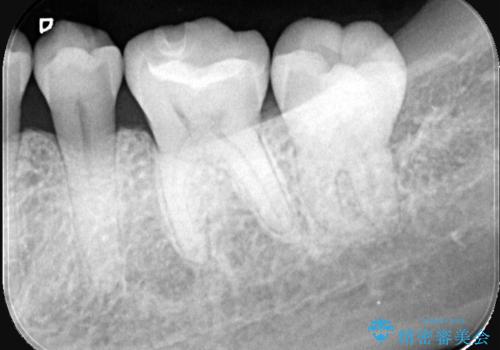

歯が欠けたことによるものか、もしくは以前装着された修復物の不適合が原因と考えられますが、銀歯(メタルインレー)と歯との間に大きな段差が認められ、汚れが溜まりやすい状態となっていました。

このような状態では、修復物の内部で虫歯が進行している可能性が高いため、治療が必要と判断しました。

今回は、経年的な劣化が少なく、汚れが付着しにくいセラミックインレーを用いて治療を行いました。